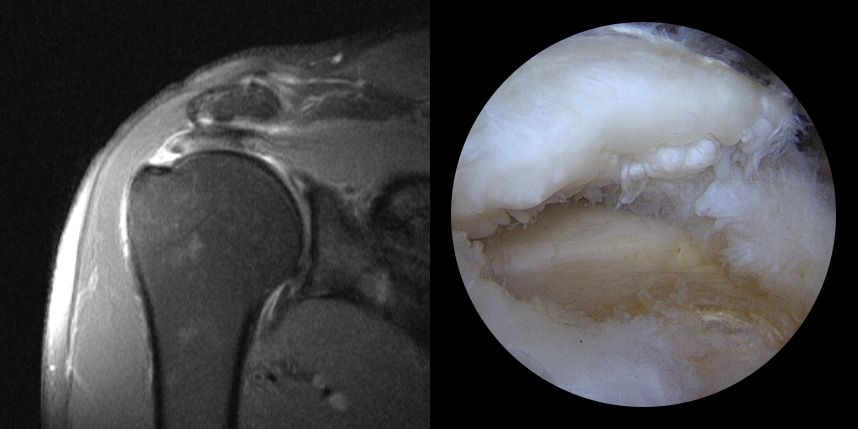

MRI상 회전근개 파열이

진행되는 경우

완전 파열시

브릿지 봉합술